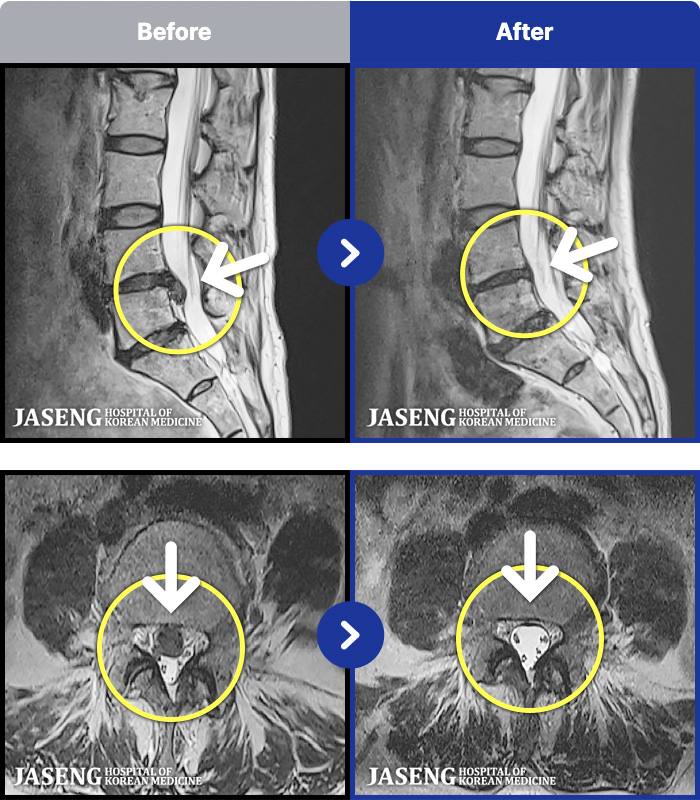

MRI ġ

1,299 MRI ũ ʸ Ȯϼ.